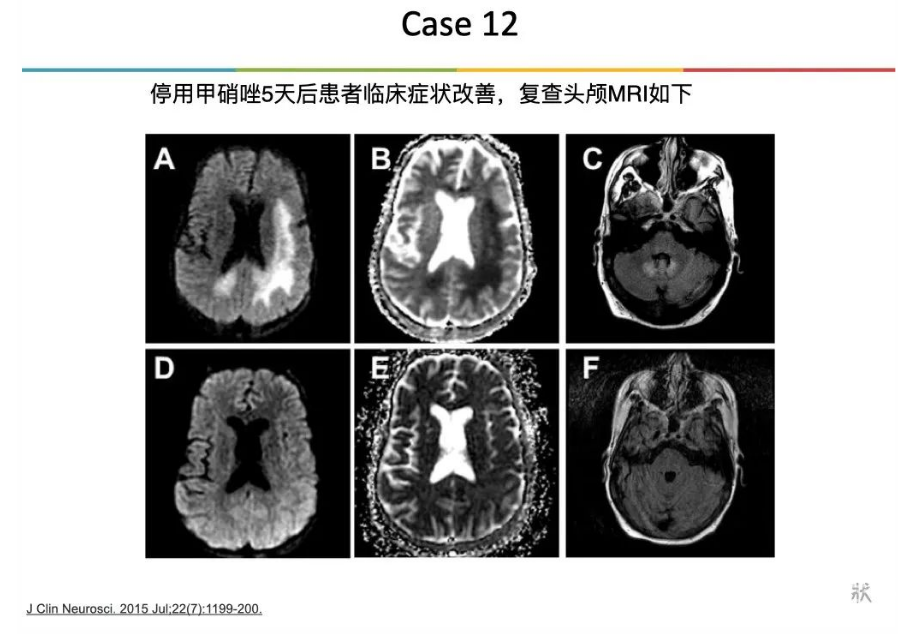

更多知识 Metronidazole is a well-recognized neurotoxin associated with peripheral neuropathy as well as encephalopathy, cerebellar dysfunction and seizures. Particularly vulnerable neural substructures include the splenium of the corpus collosum, dentate nuclei, as well as the brainstem, with concomitant symptoms of confusion, dysarthria, ataxia and nystagmus. Typically, lesions are bilateral and symmetric. Diffusion weighted imaging restricted diffusion associated with decreased ADC map, as was observed in our patient, is rare, as are focal symptoms such as gaze deviation, aphasia and hemiplegia. In a recent review of the literature, 64 patients with metronidazole toxicity were identified and only 11 had subcortical white matter tract involvement. Most patients had cerebellar dysfunction (75%) and many had encephalopathy (33%) or seizures (13%). 甲硝唑是一种公认的神经毒素,与周围神经病、脑病、小脑功能障碍和癫痫有关。易受损的神经亚结构包括胼胝体压部、齿状核和脑干,并伴有意识模糊、构音障碍、共济失调和眼球震颤等症状。通常情况下,病变是双侧对称的。该患者的影像学改变(DWI高信号和相应的ADC图低信号)以及局灶性症状,如凝视偏差,失语症和偏瘫是罕见的,2008年一篇文献综述中,共纳入64名甲硝唑中毒性患者,只有11名患者皮质下白质束受累。大多数有小脑功能障碍(75%),脑病(33%)或癫痫(13%)。 Consistent with prior case reports, this man’s symptoms and MRI changes resolved after discontinuation of metronidazole. While acute onset of hemispheric symptoms often suggests stroke or seizure, this patient demonstrates the importance of maintaining metabolic dysfunction (metronidazole toxicity) in the differential diagnosis. 与以前的病例报告一致,该患者的症状和MRI改变在停用甲硝唑后消失。急性发作的半球症状通常提示脑卒中或癫痫发作,该病例说明代谢功能障碍(甲硝唑中毒)在脑卒中鉴别诊断中的重要性。 声明:脑医汇旗下神外资讯、神介资讯、神内资讯、脑医咨询、Ai Brain 所发表内容之知识产权为脑医汇及主办方、原作者等相关权利人所有。![]()